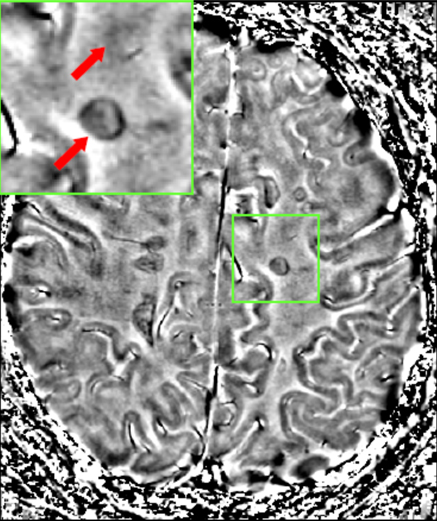

- '''뇌 영상 기술''': 기능적 자기 공명 영상(fMRI), 양전자 방출 단층 촬영(PET), 뇌파검사(EEG), 뇌자도(MEG) 등을 통해 뇌 활동을 측정한다.

- '''기능적 자기 공명 영상(fMRI)''': 뇌 혈류 변화를 감지하여 뇌 영역의 상대적인 활동을 나타낸다.